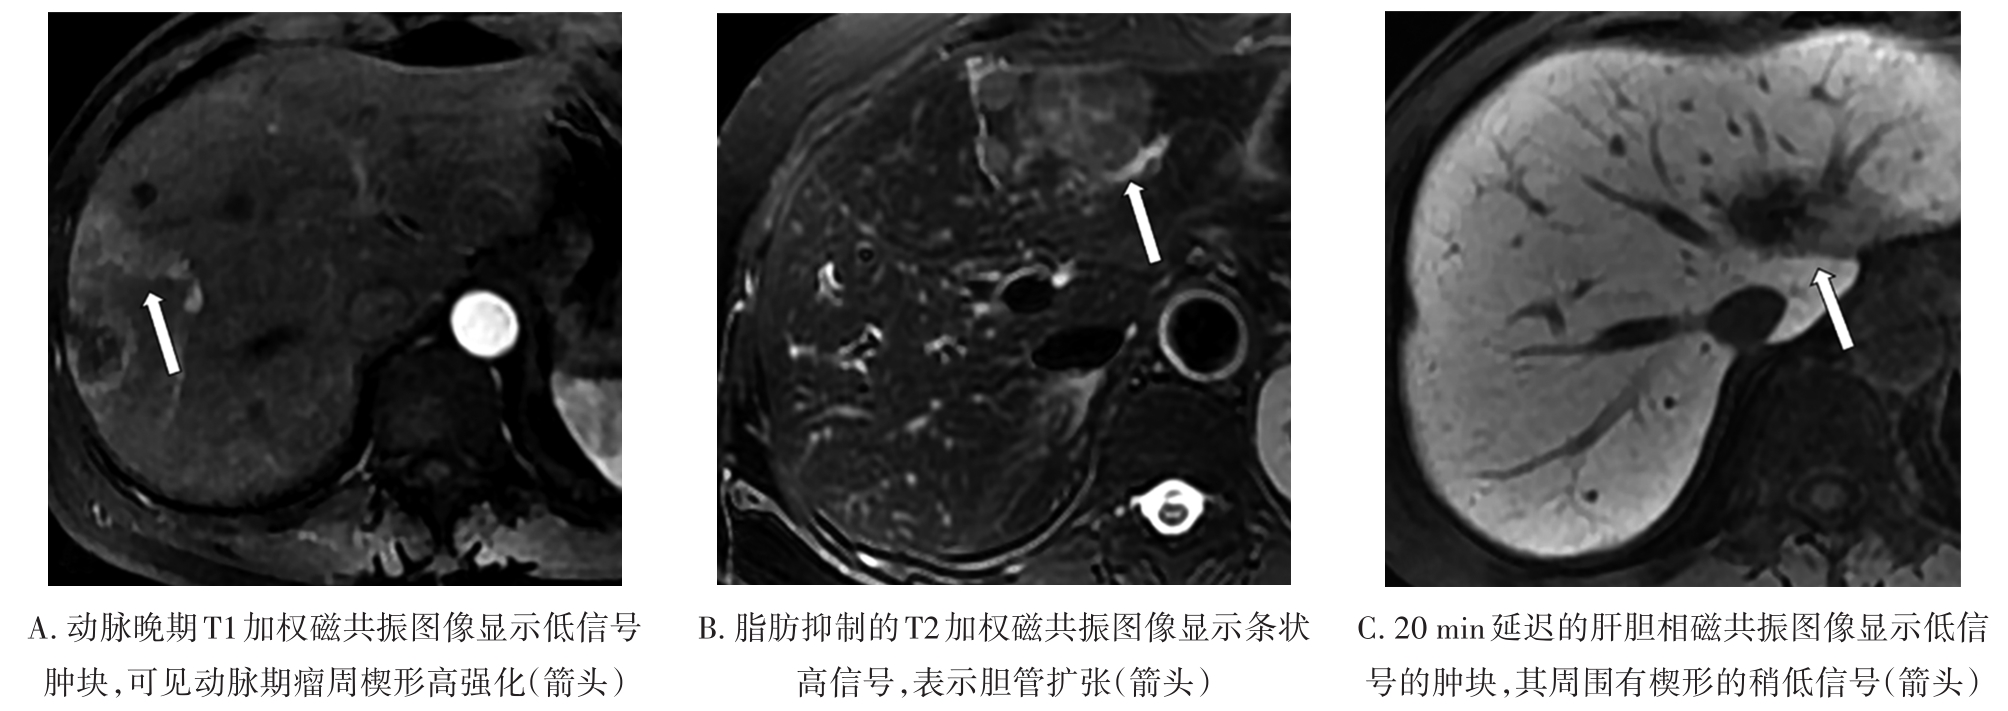

• MRI瘤周特征在预测结直肠癌肝转移非解剖性肝切除术预后的价值

2023, 48(5):548-553. DOI: 10.13406/j.cnki.cyxb.003234

摘要 (129) HTML (25) PDF 780.46 K (241) 评论 (0) 收藏

摘要:目的 研究结直肠肝转移(colorectal liver metastases,CRLM)瘤周影像特征在非解剖切除(non-anatomic resection,NAR)后CRLM患者中长期预后的价值。方法 回顾性纳入术前行腹部钆塞酸二钠增强磁共振成像(magnetic resonance imaging,MRI)和NAR术后的CRLM患者。影像特征评估动脉期瘤周高强化、肝胆期(hepatobiliary phase,HBP)瘤周低摄取和瘤周胆管扩张。应用Kaplan-Meier法计算生存率,并采用Cox比例风险回归模型进行单因素和多因素分析以确定无肝内复发生存期(liver recurrence-free survival,LRFS)、无复发生存期(recurrence-free survival,RFS)和总生存期(overall survival,OS)的独立预测因素。结果 本研究共纳入36例患者,58个CRLM病灶。存在和不存在动脉期瘤周高强化的患者3年LRFS和RFS率有统计学差异(LRFS:14.3% vs. 43.9%,P=0.005;RFS:14.3% vs. 40.3%,P=0.006)。动脉期瘤周高强化与较差的LRFS(P=0.002,HR=5.541,95%CI=1.853~15.975)和较差的RFS(P=0.002,HR=5.392,95%CI=1.887~15.412)独立相关。胆管扩张和HBP瘤周低摄取均不为LRFS、RFS和OS的独立预测因素。结论 动脉期瘤周高强化是接受NAR的CRLM患者LRFS和RFS预后因子。